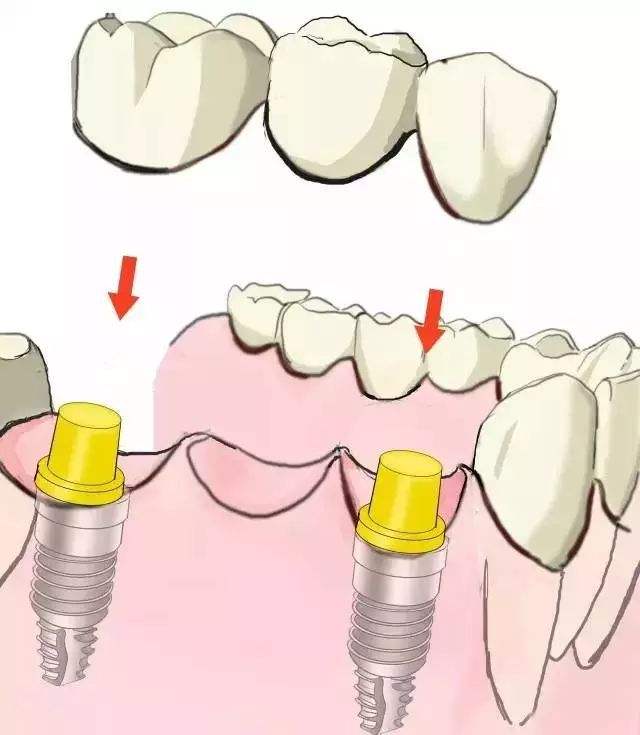

多颗牙连续缺失的种植修复方案--种植体固定桥,多颗牙缺失,当植入的种植体数目与缺牙数目相等时,每颗种植体上分担的咬合力相对较小,但植入的数量较多,相应会增加患者的经济负担,于是临床医生设计了带有桥体支持的种植体固定桥。

由于前牙区牙弓弧度较大,较少采用种植体支持固定桥的设计形式,而在后牙区,由于牙弓弧度较小,采用种植体支持的固定桥较为常见。种植体支持的固定桥可有多个单位,可以间隔出现也可连续出现,种植固定桥从理论上分析是合理的种植修复方案,它的较大好处是减少了种植体的数量,降低了成本,另外在维护种植体周围组织健康及取得共同就位道等方面也降低了难度。

温馨提示:一般情况下,种植固定桥其桥体长度不超过两个缺牙单位,桥体长度的增加是种植体-骨界面应力增加的因素之一,所以应尽量缩小桥体的长度,以减小种植体-骨界面的应力。